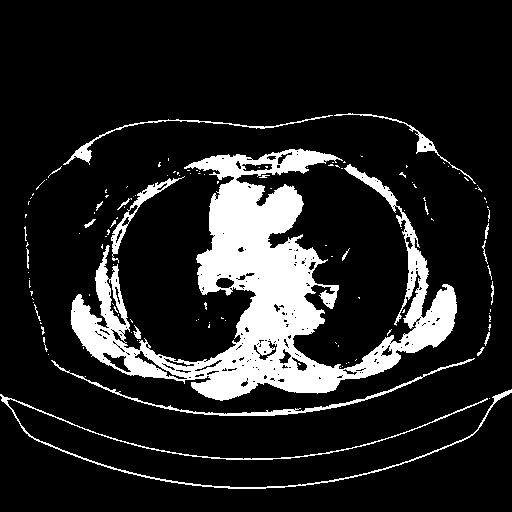

Generated VENOUS CT scan (A→B translation)

Full window (WL 1023.5, WW 4095 β†’ Low βˆ’1024, High +3071)

Actual HU range: [-1024.0, 3071.0]